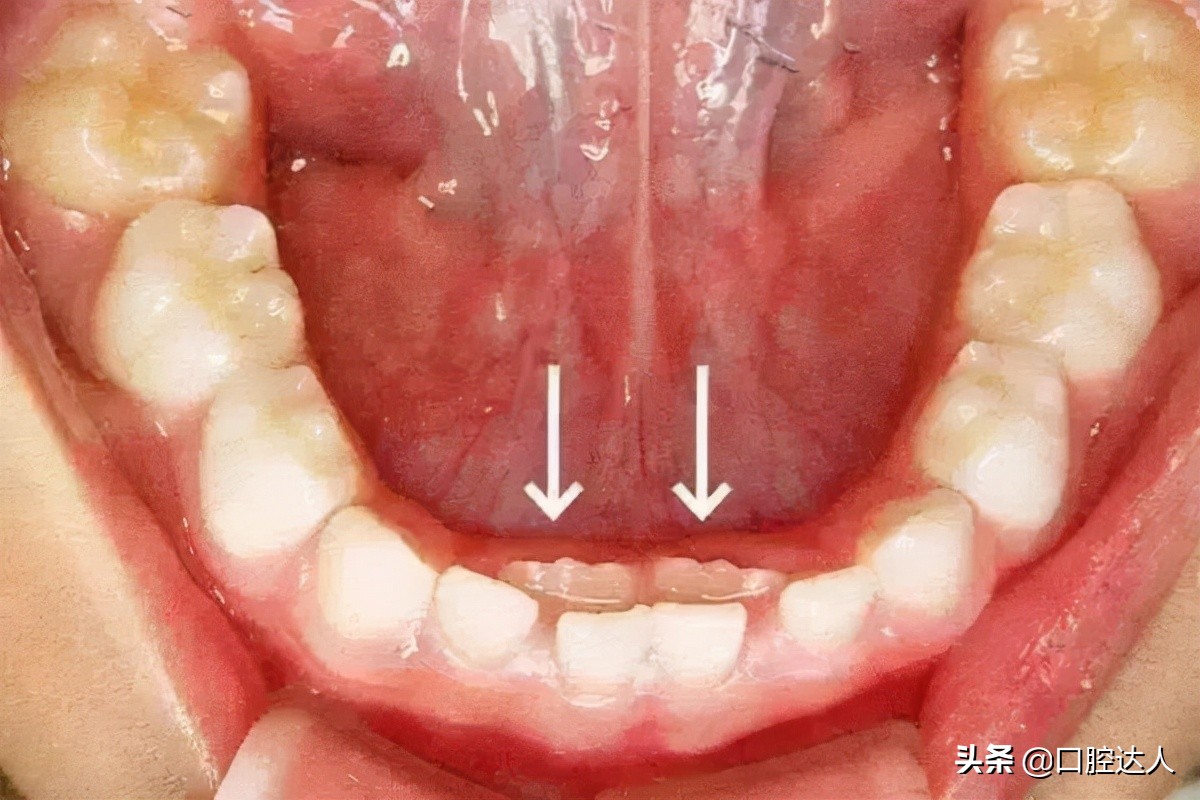

出现”双排牙“现象。这种情况就是我们所说的“乳牙滞留”。

箭头所指为恒牙

1.继承恒牙已萌出,而乳牙未脱落,称早期滞留;

2.恒牙未萌出,但已超正常换牙年龄极限仍未脱落的乳牙,称晚期滞留;